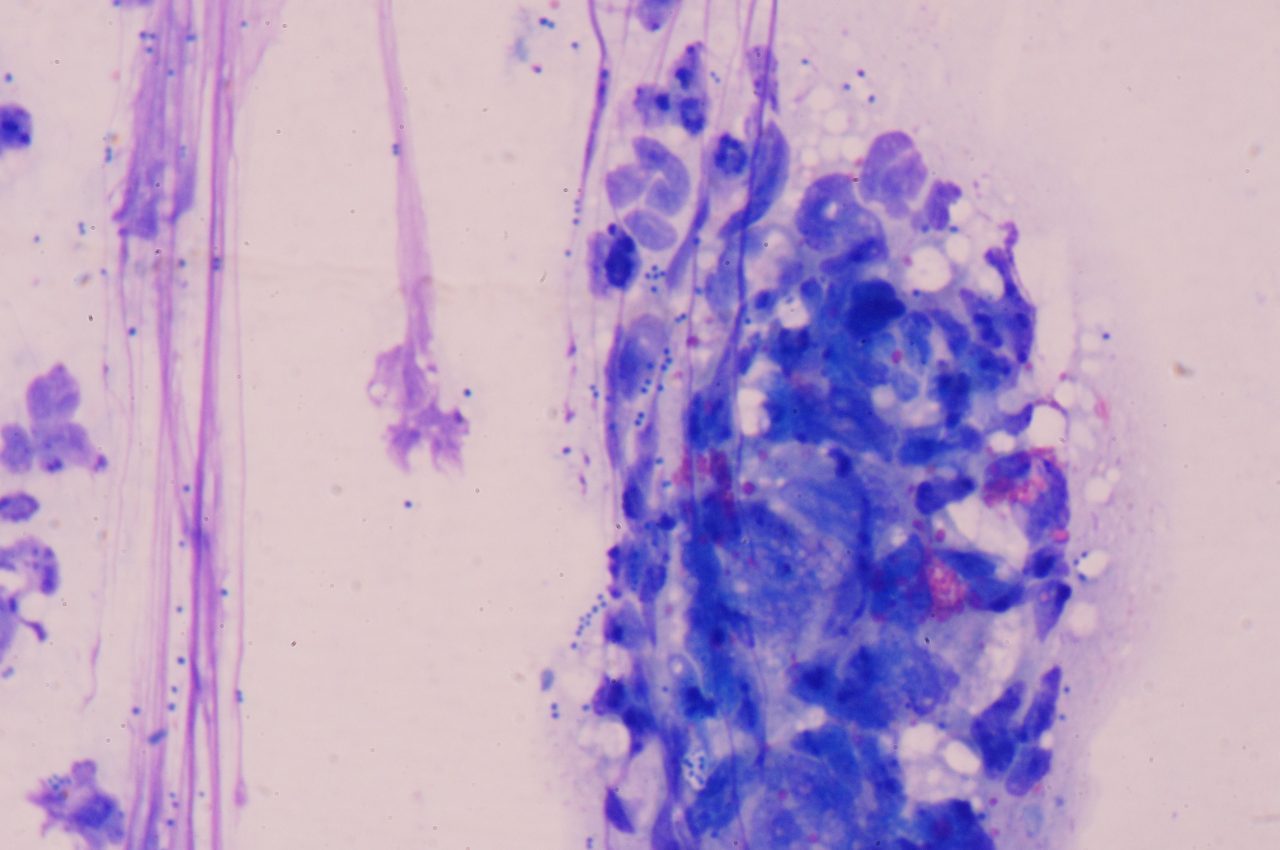

シワの部分のスタンプ検査にて、球菌と変性好中球を確認。

細菌感染を伴った、皺壁性皮膚炎と診断しました。